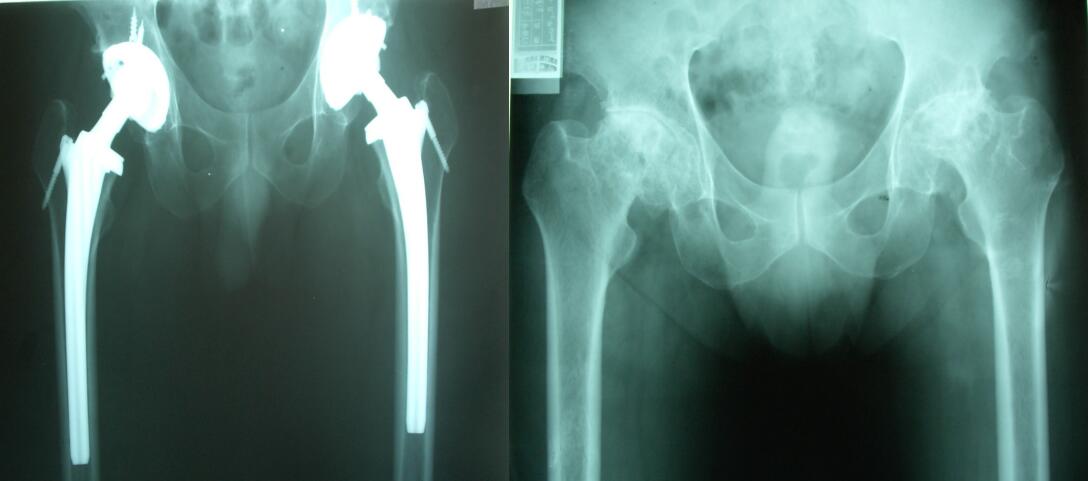

關(guān)節(jié)置換示意圖

更多成功手術(shù)案例展示:

髖關(guān)節(jié)關(guān)節(jié)置換